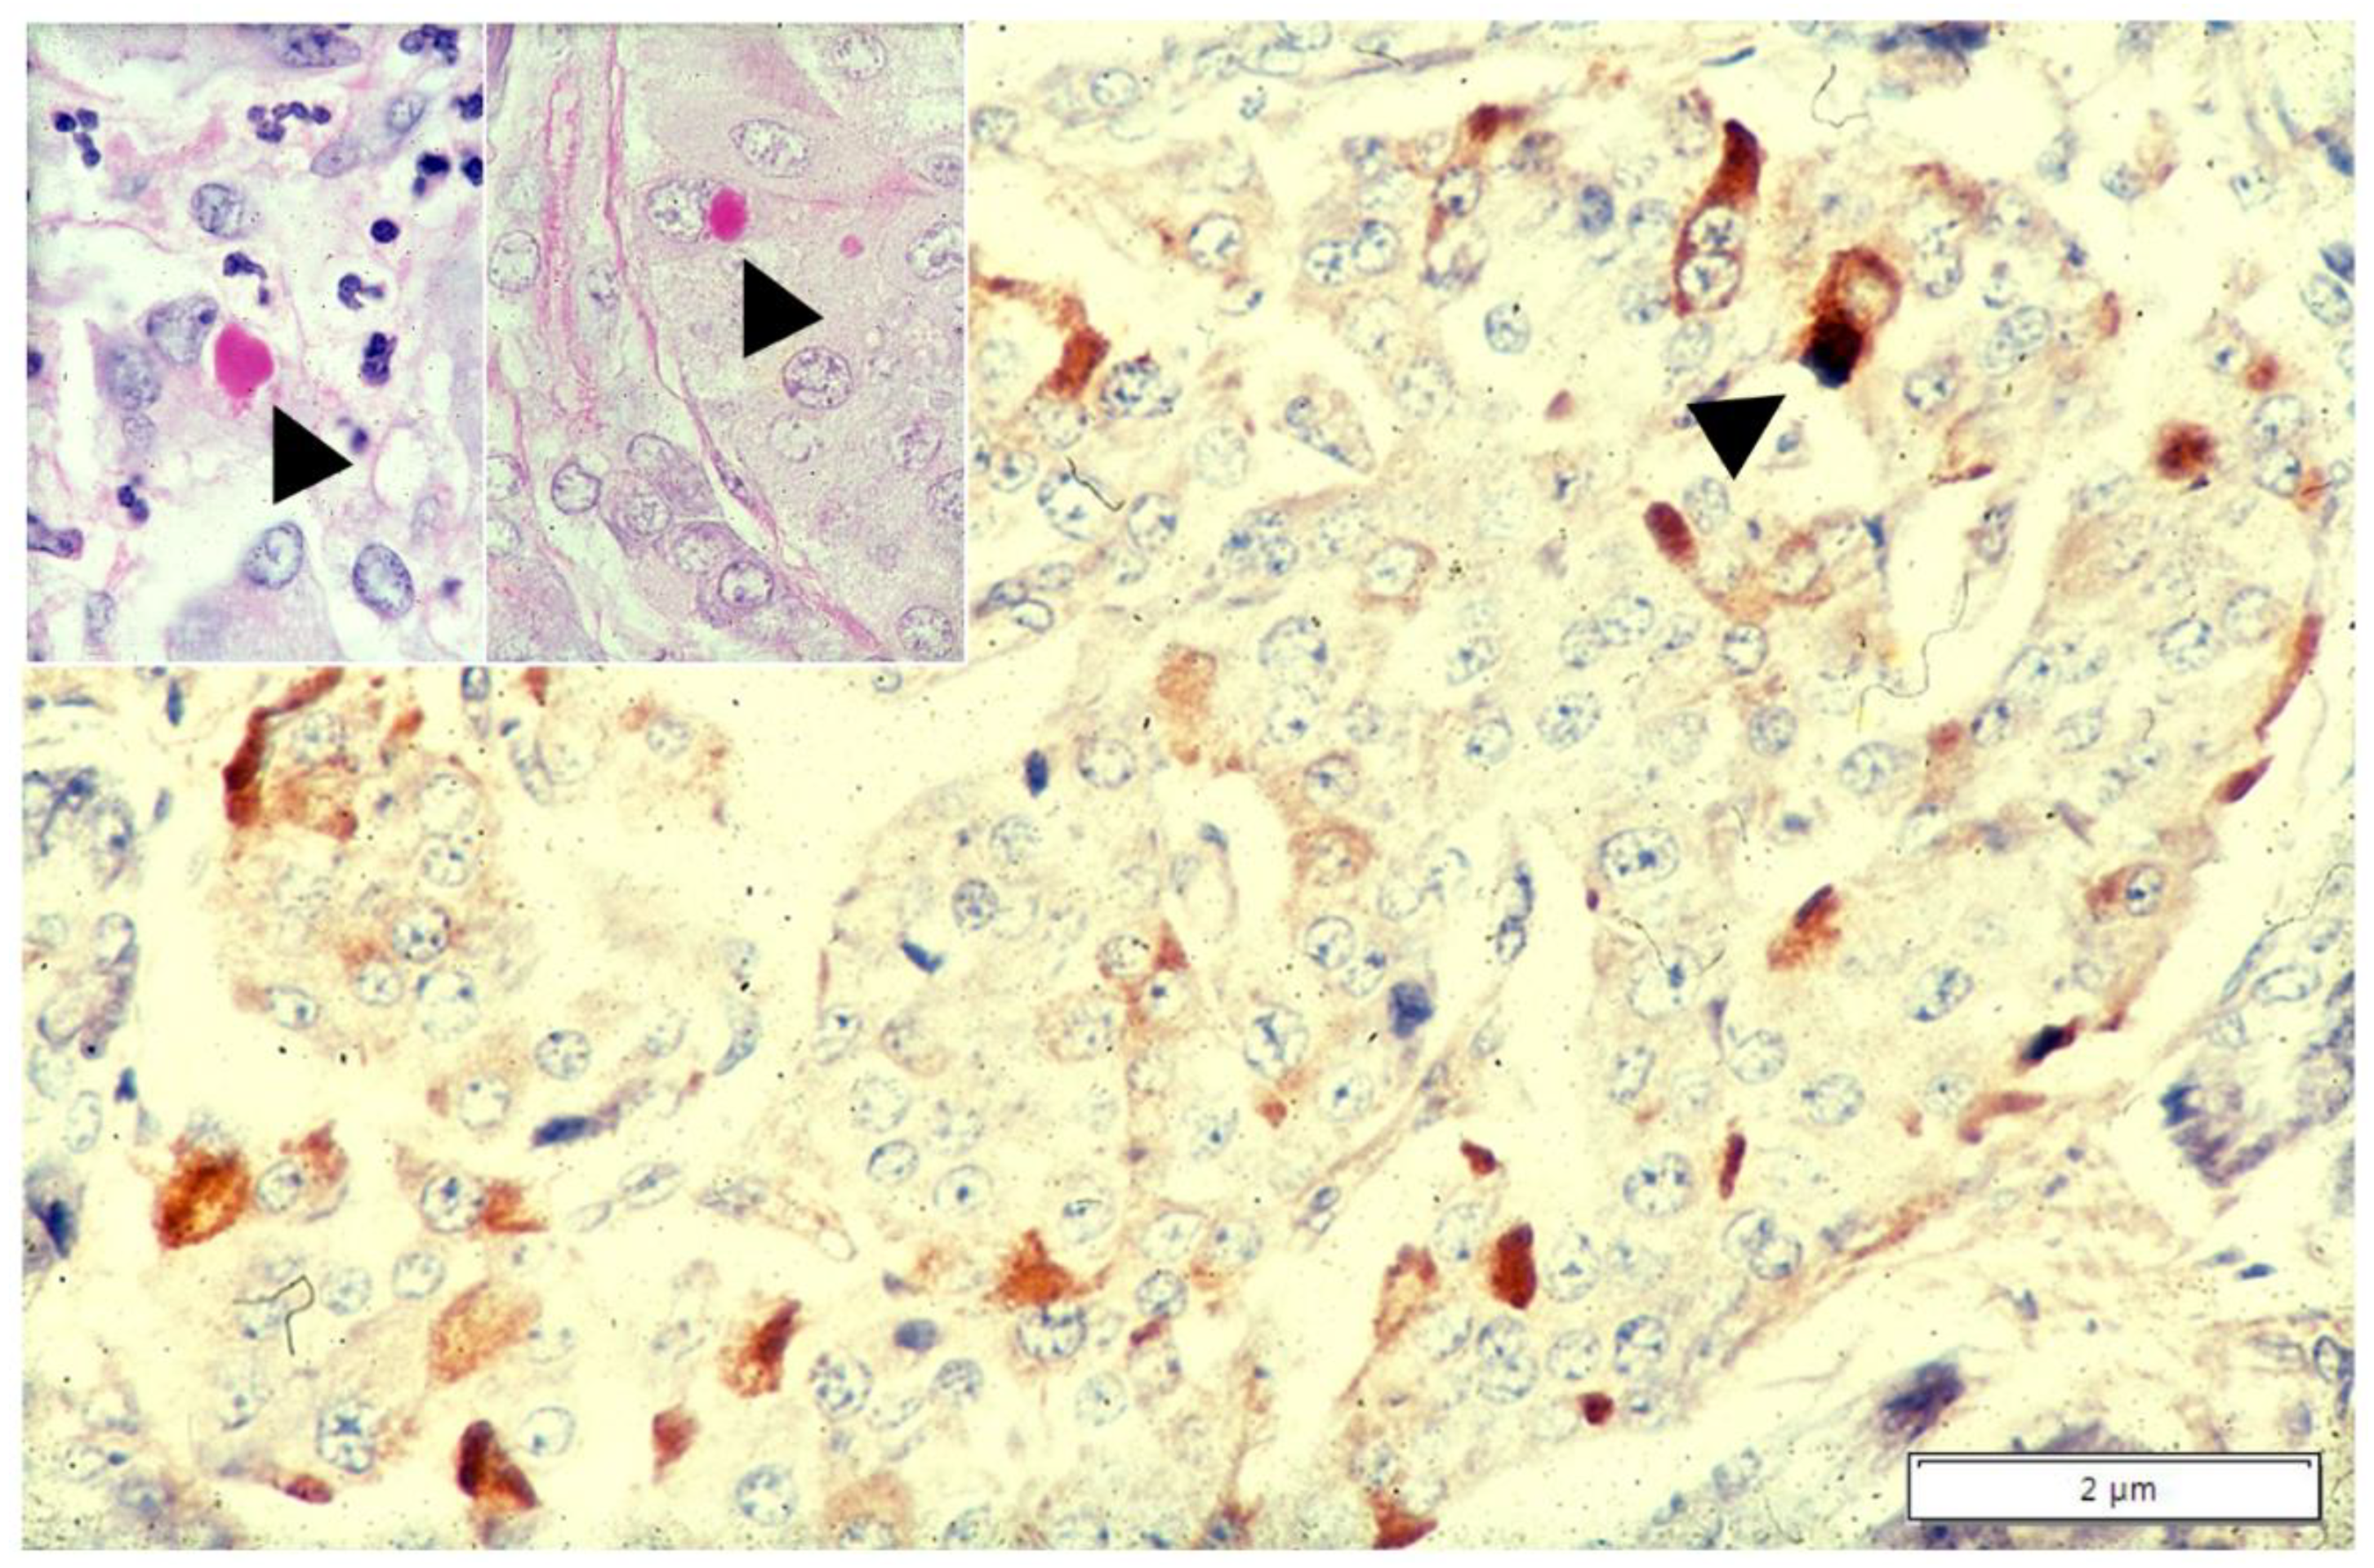

To synthesize, the consistently AAT positive staining in islet and paracrine pancreas (Figure 8) and in Kuppfer cells (Figure 5b) of Pi MM individuals strongly supports the interpretation that AAT is not a protein for secretion in those cells (44). On the other hand, the simultaneous accumulation of Z AAT in hepatocytes, pancreatic islet (Figure 9) and Kupffer cells (Figure 6), indicates a primary synthesis in all these cells.

Figure 9.

Pi ZZ cirrhotic patient. A pancreatic islet shows AAT positive cells mainly located at the periphery (immunostaining × 100). An islet cell (head arrow) contains a large AAT immunoreactive globule (arrow-head) corresponding to the PAS–D inclusion at the apical pole of the same cell (inset: arrowhead, PAS–D × 100)). An analogous inclusion is present in a hepatocyte surrounded by inflammatory cells, from the cirrhotic liver of the same patient (PAS–D, original magnification 100×).